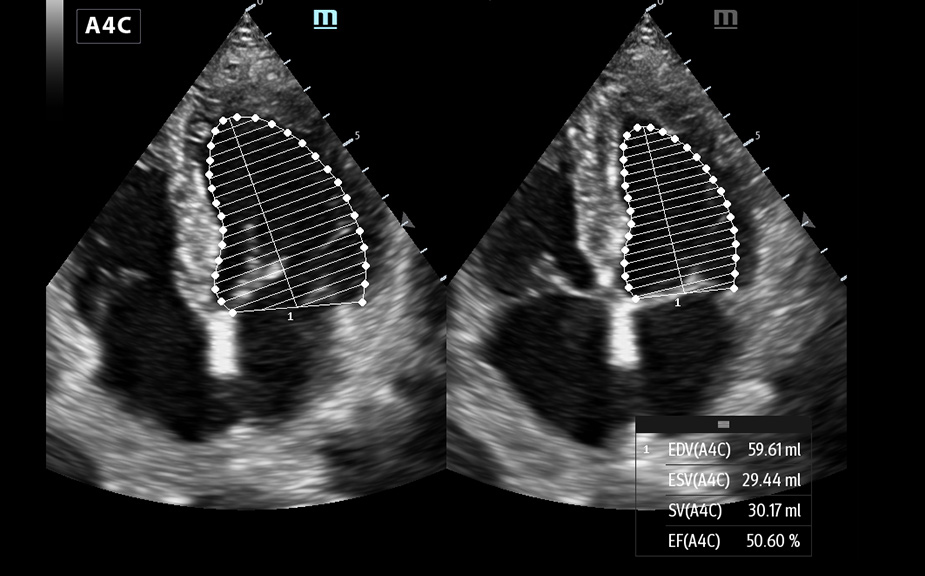

Obrazy kliniczne